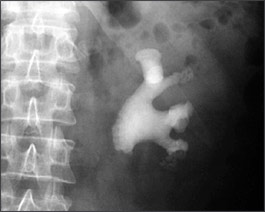

Staghorn calculi represent a less-common nephrolithiasis subgroup so named because the significant stone burden that fills the renal pelvis and calyces forms a shape on radiographs that resembles a deer’s horns. Most staghorn stones in Western society are composed of struvite and can cause significant morbidity and mortality if left untreated; therefore, large struvite stones must typically be removed.

Staghorn calculi, also sometimes called coral calculi, are renal calculi that obtain their characteristic shape by forming a cast of the renal pelvis and calyces, thus resembling the horns of a stag.